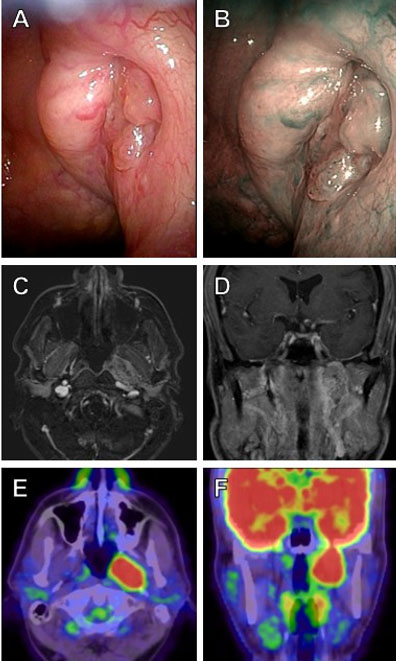

At the initial visit to our hospital, a tumor was observed at the pharyngeal orifice of the ET (Figure 2A and Figure 2B). Magnetic resonance imaging (MRI) revealed a 34 mm enhancing lesion along the ET (Figure 2C and Figure 2D), with corresponding FDG uptake on PET-CT (Figure 2E and Figure 2F). Biopsy from the tumor at the pharyngeal opening also confirmed SCC (Figure 3). Radical chemoradiotherapy (CDDP 100 mg/m2 × three times, RT S60 Gy) led to complete remission without grade 3 or higher toxicity. The patient remains disease-free at five years, and tympanoplasty was later performed for residual perforation.

Figure 2: Radiological findings at our hospital. (A, B) Nasopharyngeal fiberscope. (C, D) Contrast-enhanced MRI. (E, F) PET-CT. Endoscopy revealed a mass slightly protruding from the pharyngeal orifice of the ET (A), with no abnormal vascular structures detected (B). A 34 × 20 × 34 mm mass lesion was observed on MRI (C, D), consistent with the course of the left ET, with corresponding FDG uptake on PET-CT (E, F). There was no evidence of cervical lymph node metastasis or distant metastasis.